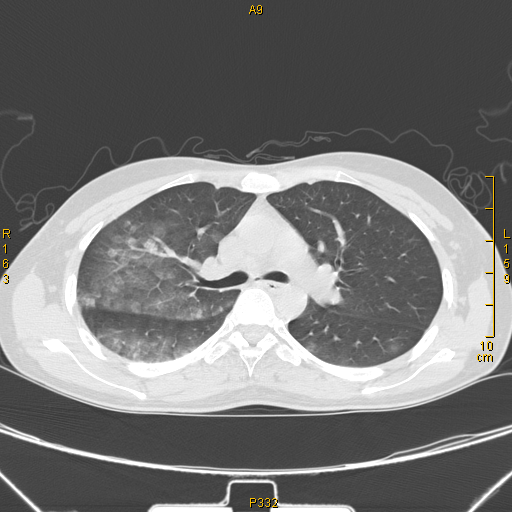

病例68——肺部典型病例(吸入性肺炎)

吸入性肺炎病例收集